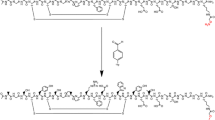

Figure 1 shows the chemical structure of 18F-FACT. The radiochemical purity of the radioligand in the present clinical study ranged from 97.8% to 98.7% (mean ± SD, 98.33 ± 0.42%). The specific radioactivity ranged from 30.6 to 347.7 GBq/μmol at the time of injection (mean ± SD, 139.9 ± 116.2 GBq/μmol).